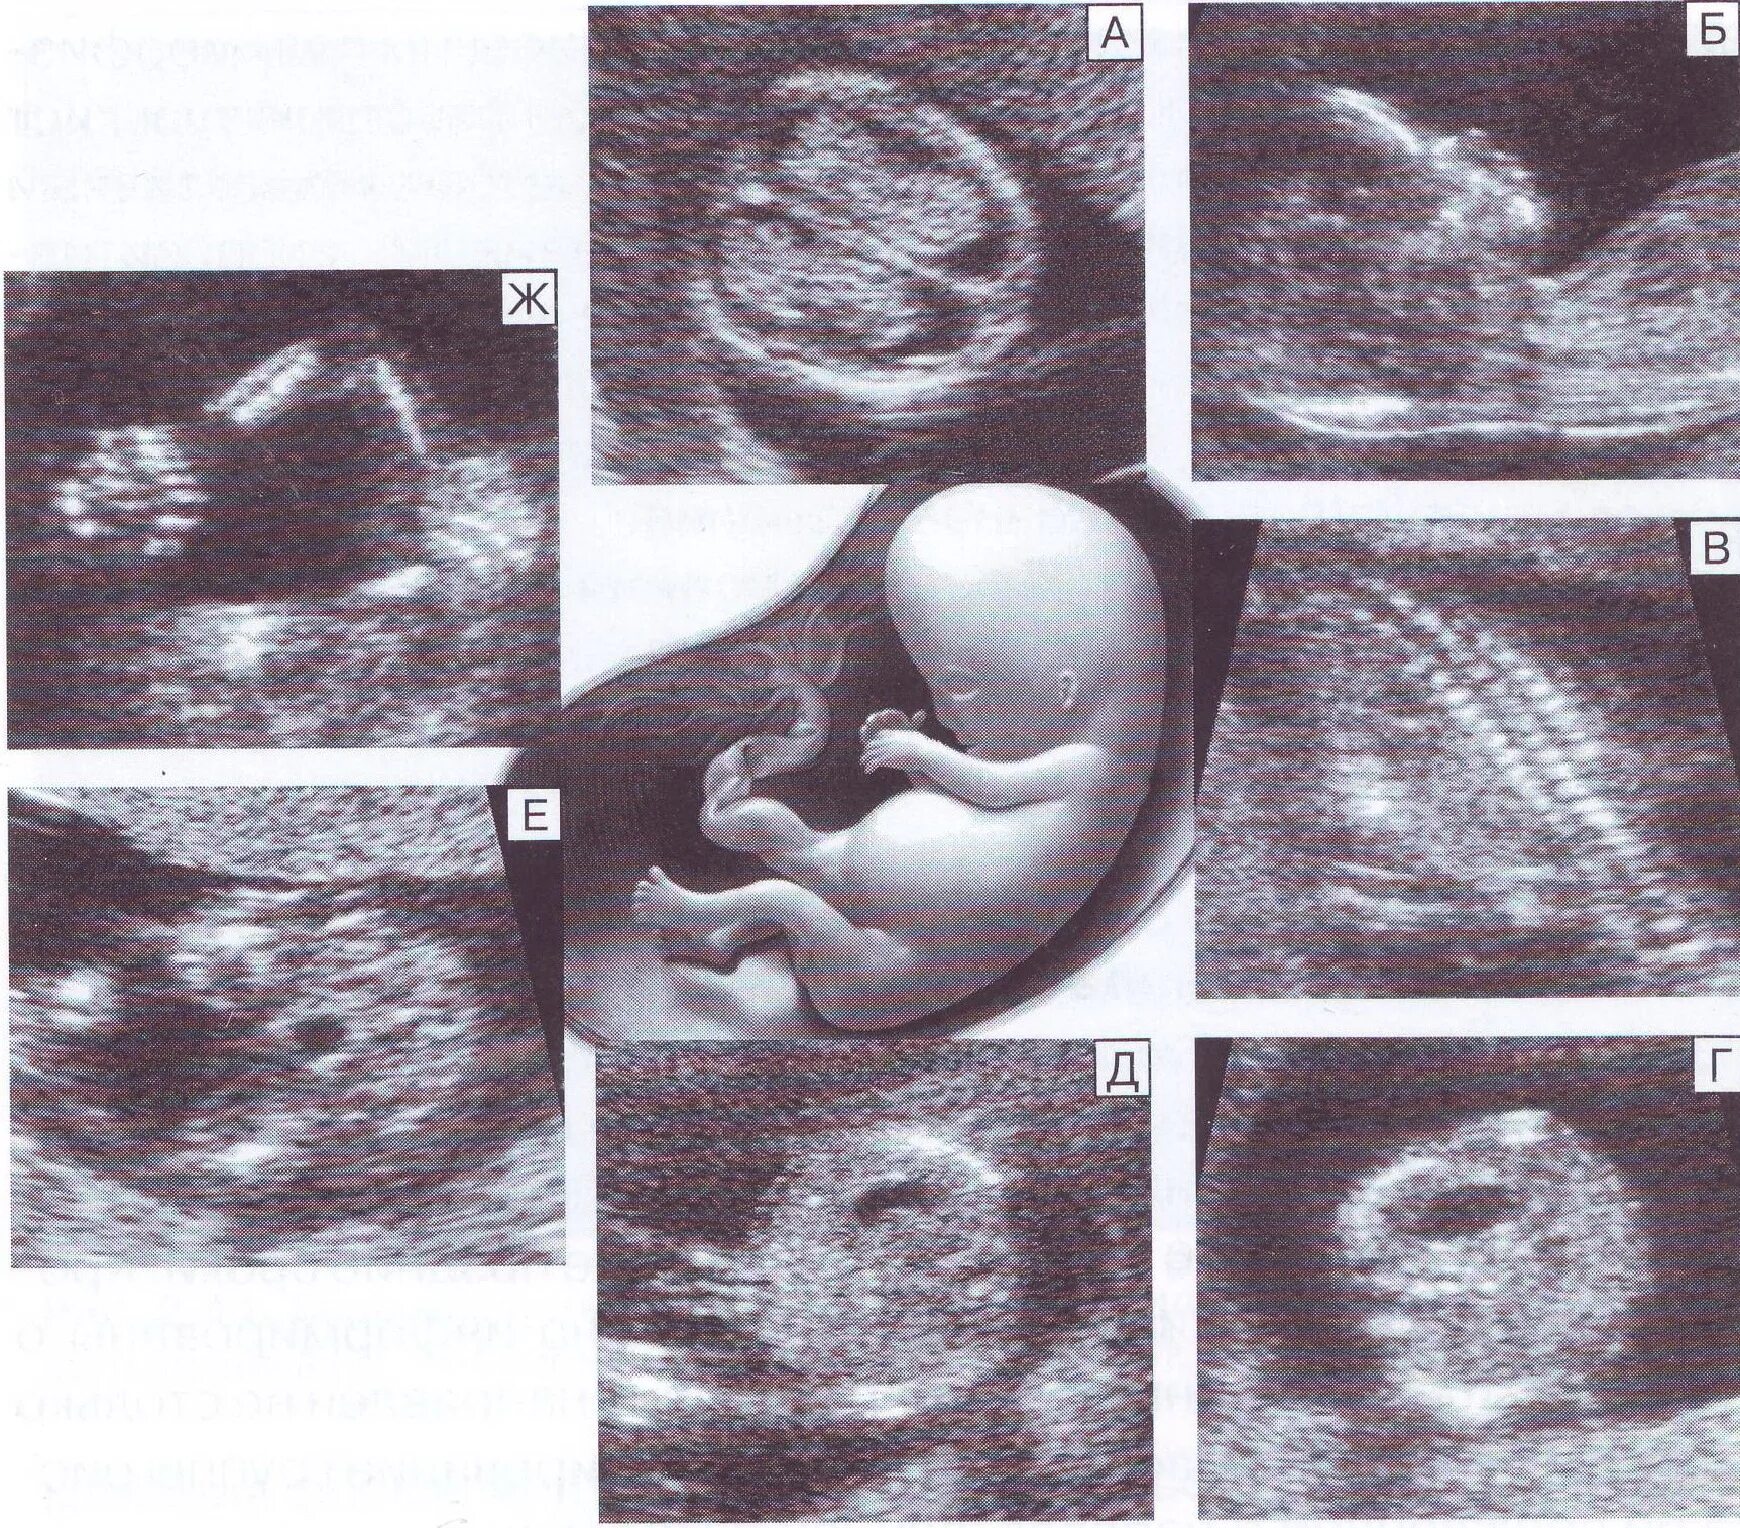

Малыш на первом скрининге